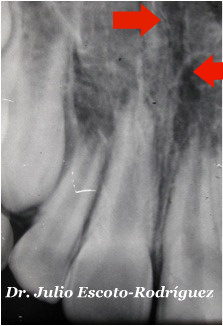

| Acompaña al referimiento una Rx. Periapical donde se observa una línea radiolúcida a nivel medial (sutura media palatina). Por lo que decidimos tomar una radiografía oclusal. |